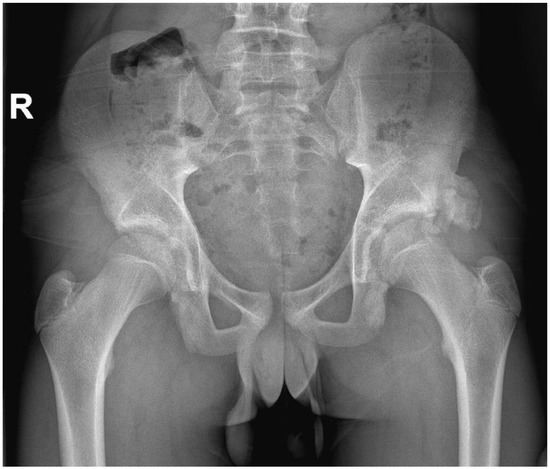

| 1 | 12 | Male | R | None | Kicking a ball | X | 5 mm | NA |

| 2 | 13 | Male | R | None | Kicking a ball | X/CT | 15 mm | 3 |

| 3 | 13 | Male | R | None | Kicking a ball | X/US | 0 mm | 2 |

| 4 | 13 | Male | L + R | Yes | No trauma | X | 0 mm | Unknown * |

| 5 | 15 | Male | R | None | Kicking a ball | X | 8 mm | 2 |

| 6 | 16 | Male | L | None | Fall on knee | X/MRI | 10 mm | 3 |

| 7 | 17 | Male | L | Yes | Jump | X/CT | 10 mm | 3 |